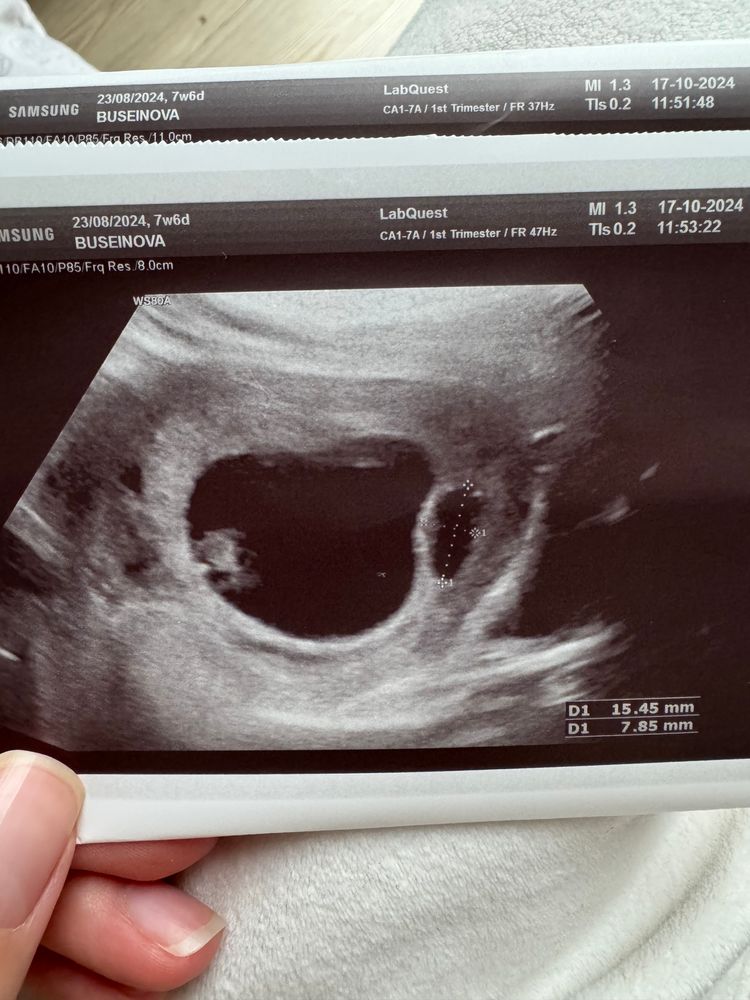

Два плодных яйца, одно маленькое

Беременность 5 недель Два плодных яйца, одно гораздо меньше

Конечно есть шанс что вырастет и второе срок совсем маленький. В 5,3 обычно плодное 3-4 мм. Просто возможно было две овуляции с ращницей в неделю

15мм это наоборот большое для 5,3. Скорее всего овуляция одна рано вторая поздно